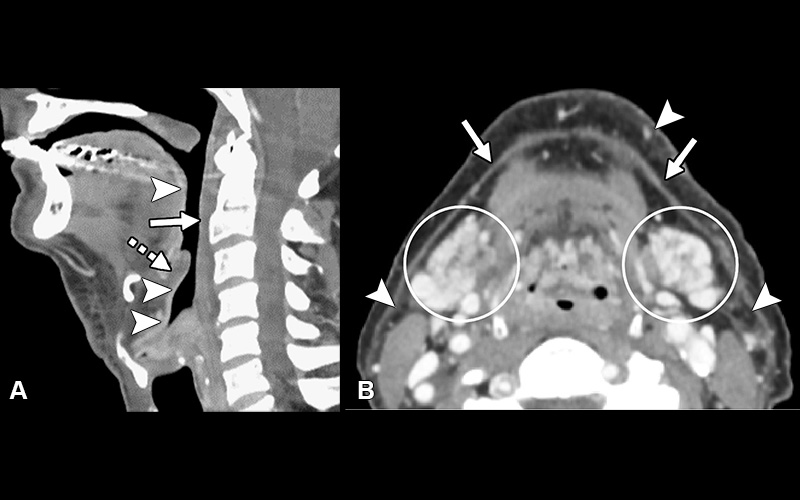

Postradiation-related changes—acute findings. (A) Sagittal postcontrast CT image demonstrates retropharyngeal edema (solid arrow), laryngeal mucoid edema (dashed arrow), and intense linear mucosal enhancement (arrowheads). (B) Axial postcontrast image demonstrates edema and intense enhancement of the submandibular glands (circled), thickening of the platysma muscle (arrows), and stranding of the fat (arrowheads).